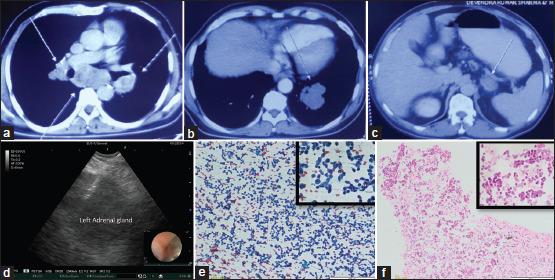

Endobronchial ultrasound-guided transbronchial needle aspiration (EBUS-TBNA) is a standard-of-care modality for evaluating mediastinal lymph nodes and masses. The EBUS bronchoscope may also be introduced through the oesophageal route to perform sampling of accessible lesions, a technique described as transoesophageal bronchoscopic ultrasound-guided fine-needle aspiration (EUS-B-FNA). Because of the central oesophageal approach, EUS-B-FNA provides easy access to the left para-tracheal, subcarinal and para-oesophageal lymph nodes. In addition, the left adrenal gland (LAG) can also be imaged and sampled during the EUS-B-FNA procedure. In patients with suspected lung cancer, accurate staging is essential. Adrenal metastasis is relatively common and may often be a solitary metastatic site. We describe three cases where EUS-B-FNA was performed to safely sample the enlarged LAG in suspected lung cancer. We also review the literature on the performance characteristics of EUS-B-FNA for LAG aspiration.

支气管内超声引导下经支气管针吸活检术(EBUS-TBNA)是评估纵隔淋巴结和肿块的标准治疗方式。EBUS支气管镜也可经食管途径插入,对可触及的病变进行采样,该技术称为经食管支气管镜超声引导下细针穿刺活检术(EUS-B-FNA)。由于采用经食管中心入路,EUS-B-FNA能够轻松到达气管旁左侧、隆突下及食管旁淋巴结。此外,在EUS-B-FNA操作过程中,还可对左肾上腺(LAG)进行成像和采样。在疑似肺癌患者中,准确分期至关重要。肾上腺转移相对常见,且常可能是唯一的转移部位。我们描述了3例通过EUS-B-FNA对疑似肺癌患者肿大的LAG进行安全采样的病例。我们还回顾了关于EUS-B-FNA对LAG穿刺活检性能特征的文献。